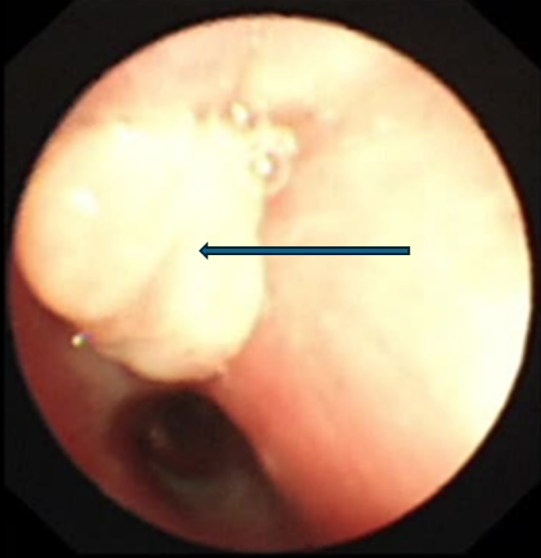

箭头为右主支气管高密度影。

父母带乐乐到一家医院就医,CT检查结果显示(图1),乐乐右主支气管有可疑阴影,右侧肺还有个肺大泡,经评估病情复杂。父母火速将其送到广州医科大学附属妇女儿童医疗中心急诊科。

支气管镜检查显示右上叶支气管肉芽增生,完全堵塞开口